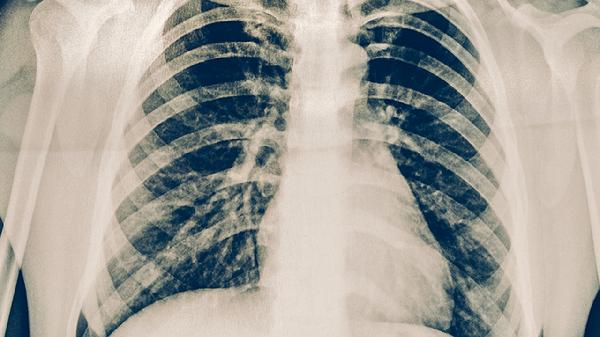

伤后1周、2周、4周分别进行X线复查,观察骨痂生长情况。多发性骨折需每月复查CT直至愈合,延迟愈合者需考虑体外冲击波治疗。康复期逐步开始肩关节环转运动,6-8周后可尝试游泳等低冲击运动。